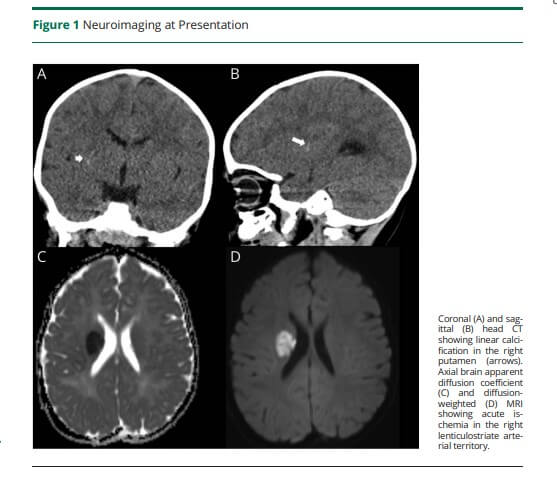

El artículo describe el caso de un lactante previamente sano que desarrolla déficits motores tras un golpe menor. A las cinco horas, una tomografía computarizada (CT) revela una calcificación lineal en el putamen (estructura del cerebro) derecho. Ocho horas después, una resonancia magnética con secuencias de susceptibilidad (SWI) confirma un ictus agudo en el territorio de la arteria lenticuloestriada derecha.

Lo relevante de esta imagen es que, mediante técnicas de fase filtrada, se logran distinguir pequeñas calcificaciones en el estriado derecho, imposibles de detectar por métodos convencionales. Esto permite diferenciar claramente entre presencia de sangre y depósitos de calcio, característicos de la angiopatía mineralizante.

Como se describe en el estudio, la angiopatía mineralizante infantil es una condición que afecta las arterias pequeñas del cerebro, predisponiendo a los niños a sufrir ictus tras traumatismos leves. Aunque puede confundirse con calcificaciones fisiológicas propias de la edad, su distribución lineal en regiones específicas (como los ganglios basales) permite identificarla correctamente.

Los estudios de angiografía por resonancia magnética (MRA) intracraneal y cervical fueron normales, lo que refuerza la hipótesis de una patología microvascular no relacionada con malformaciones mayores.